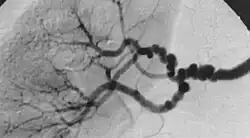

| The "string-of-beads" feature in multi-focal fibromuscular dysplasia. The sign is caused by areas of relative stenoses alternating with small aneurysms. | |

Multi-focal (previously known as medial) fibroplasia involves thickening of the media and collagen formation. It is typically reported as having the appearance of a "string of beads" on angiographic review.[4] "The 'bead' component is often larger than the normal arterial lumen, and in a subset of patients with FMD, aneurysms are present that may require treatment."[4] The multi-focal subtype of FMD accounts for nearly 80% to 90% of all FMD cases.[4]

FMD is currently diagnosed through the use of both invasive and non-invasive tests.[10] Non-invasive testing includes duplex ultrasonography, magnetic resonance angiography (MRA), and computed tomography angiography (CTA).[4] Invasive testing through angiography is considered the best way to detect FMD, though it is typically not done early in the diagnosis process due to the higher risk of complications. Occasionally, FMD is diagnosed asymptomatically after an unrelated x-ray presents the classic "string of beads" appearance of the arteries, or when a practitioner investigates an unexpected bruit found during an exam. As part of the diagnosis process, a practitioner may review medical and family history and perform vascular examination.

The differentiating presentations are suggestive of FMD being a unique syndrome in respect to the pediatric population. Experienced FMD clinicians warn against relying on the "string of beads" angiography for a diagnosis.It is suggested that FMD may be both under and over-diagnosed in children with stroke.[7]